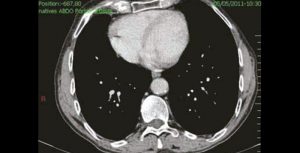

M. B., patient de 88 ans, nous explique avoir noté l’existence d’une dysphagie, ou plutôt d’un problème dyspeptique (avec parfois une régurgitation d’une partie du bol alimentaire) favorisé par la prise d’une alimentation solide. Cette problématique est apparue…